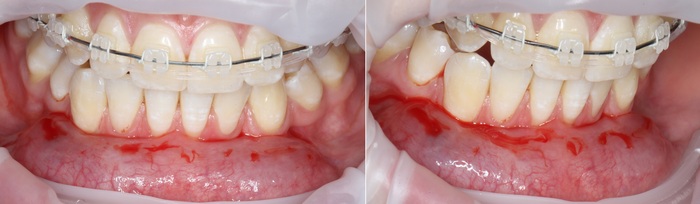

2 – проведение пластики десны.

Был взят трансплантат в области бугра верхней челюсти (это то место, где раньше был зуб мудрости).

Далее проведена пластика десны, снова два месяца ожиданий и установка временной коронки: